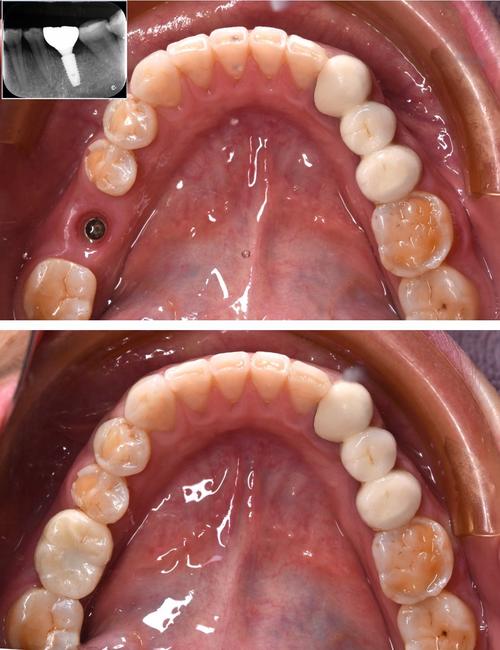

- 植入种植体:局部麻醉下,切开牙龈,暴露牙槽骨,逐级备洞后植入种植体,缝合伤口,手术时间约30分钟-1小时/颗。

- 安装基台与牙冠:骨结合后,二次切开牙龈,连接基台,取模制作牙冠,试戴调整后粘固,完成修复。